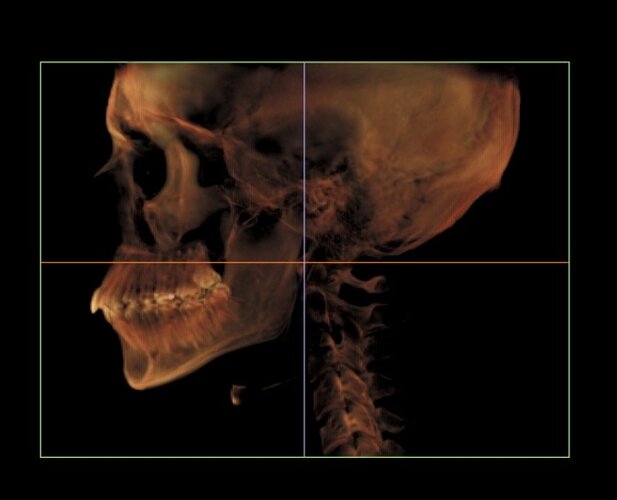

Went to the orthodontist the other day and got these scans. I’m trying to figure out what I should change or improve to look better. Based on this, what do you think needs work and what can I do to improve it?